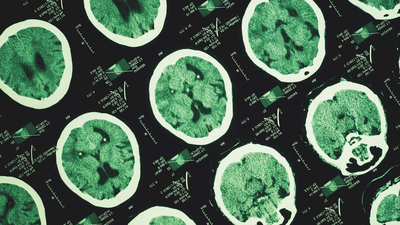

Bu kapsamda, katılımcıların bilişsel performansları her yıl ölçüldü, adım sayıları pedometrelerle kaydedildi ve beyinlerindeki amiloid ile tau protein düzeyleri PET taramalarıyla incelendi.

Buna göre, başlangıçta beyinlerinde yüksek miktarda amiloid bulunan kişilerde Alzheimer riski daha fazlaydı, ancak bu kişiler arasında daha fazla yürüyenlerde bilişsel gerileme oranı daha yavaş ve tau birikimi daha geç ilerledi.